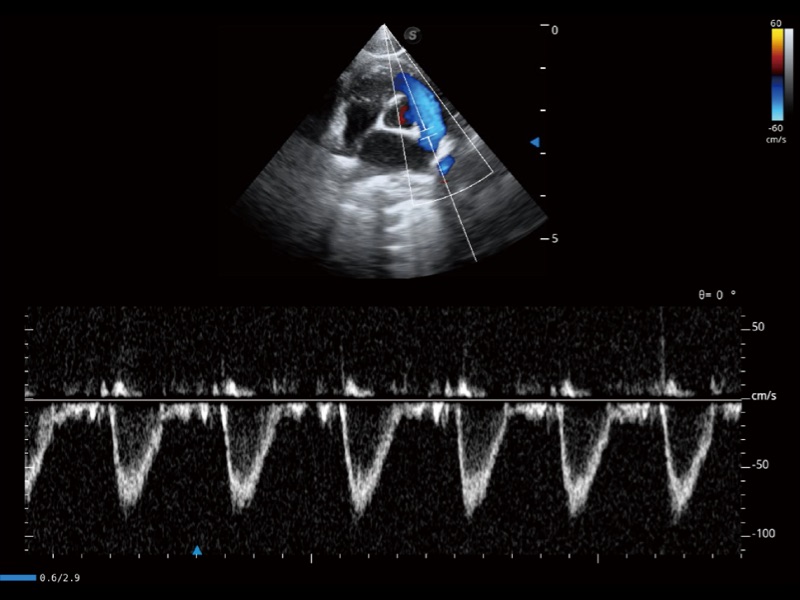

能够基于左心室壁追踪和辛普森法,自动计算射血分数,支持多个可移动点描迹,与手动测量相比,极大节省了动物医生的时间和精力。

具备多种协议可选,同时支持17阶段划分法和专业的SE报告。

通过360度任意调节3条M型取样线,在同一心动周期上观察心脏不同位置的运动曲线,得到准确的心功能测量数据,有效评估心肌运动及左心室功能。

当心脏测量结果超出正常范围时,可实时预警提示动物医生,减少疾病漏诊概率。